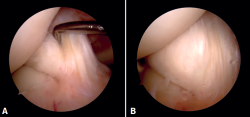

Figura 3. Visión artroscópica desde el portal anterolateral de la rodilla derecha. Se observa el quiste sinovial del ligamento cruzado anterior (LCA) en el fascículo posterolateral. A: visión con palpador diferenciando fibras del LCA sano del quiste; B: visión con la rodilla en posición “de cuatro” en la que se observa el pinzamiento del quiste en el espacio tibiofemoral lateral.

En ambos pacientes se realizó anestesia raquídea para realizar la cirugía y se utilizó manguito de isquemia a nivel del muslo. Se colocó al paciente en decúbito supino, utilizando un soporte en U en el tercio distal del muslo para la fijación de la extremidad. Se realizaron los portales artroscópicos habituales anterolateral y anteromedial, objetivando en la exploración diagnóstica de la rodilla la presencia de un ganglión localizado en el fascículo posterolateral del LCA (Figura 3) que, cuando se realizaban los movimientos de flexión y en posición de cuatro, se pinzaba en el espacio articular tibiofemoral externo. Para realizar la resección artroscópica del quiste se colocó al paciente en la posición “de cuatro”, facilitando la diferenciación anatómica de los fascículos anteromedial y posterolateral del LCA, tal y como proponen Hopper G et al.(4). Se realizó la disección y exéresis cuidadosa del quiste con una pinza basket, un terminal shaver de 4 mm y un terminal de ablación por radiofrecuencia (Figura 4). Al finalizar la resección del quiste, se realizó una nueva exploración dinámica de la rodilla, donde se evidenció la ausencia de pinzamiento entre el LCA, el cóndilo femoral y el platillo tibial lateral, a la vez que se comprobó la estabilidad del remanente del LCA (Figura 5).